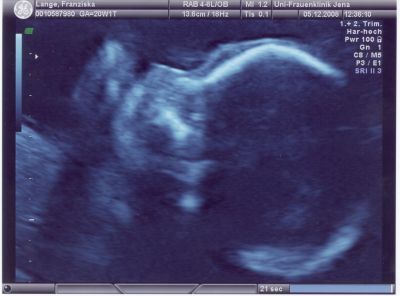

Unser Paul am 5. Dezember 2008 in der 21. Schwangerschaftswoche (6. Monat)

Unser Paulchen